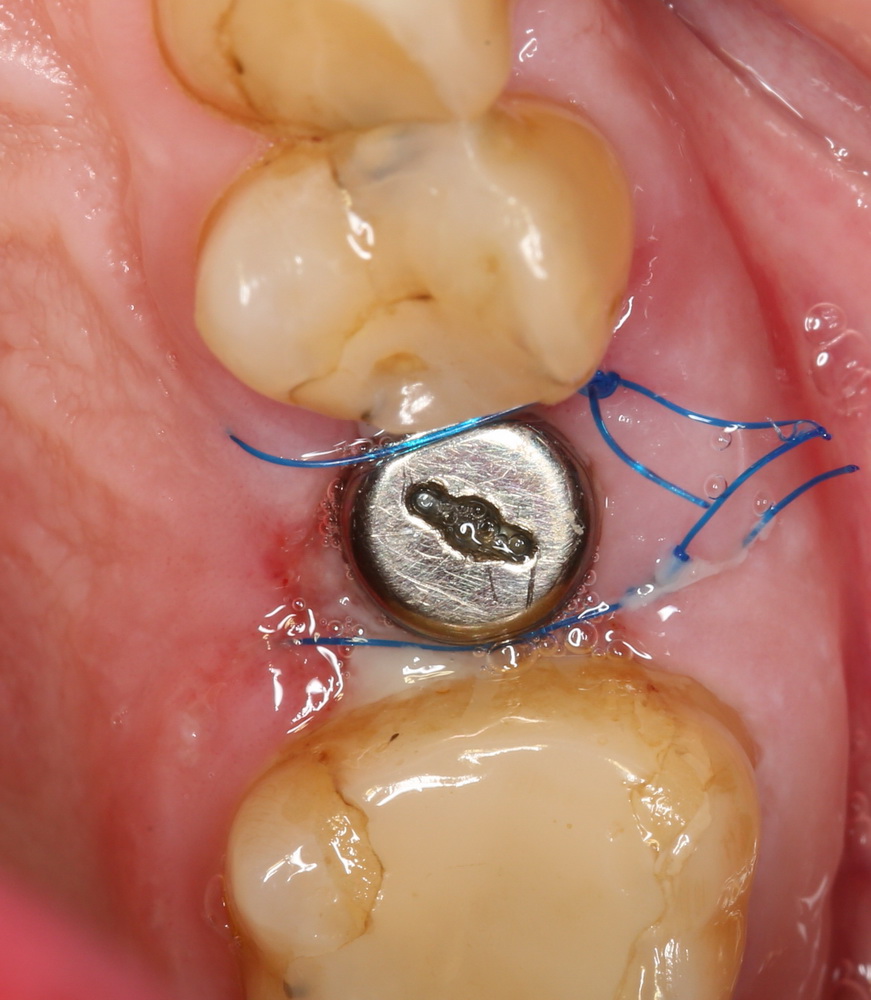

По ряду уже упомянутых выше причин, для решения этой клинической задачи мы выбрали имплантаты Xive. Лунки для них мы уже приготовили. возможную первичную стабильность оценили. Имплантаты мы установили с усилием чуть больше 15-20 Нсм — такого крутящего момента более, чем достаточно, особенно если учесть, что временные коронки будут соединяться между собой.

Подробно о том, что такое крутящий момент и хирургический протокол можно прочитать здесь>> и тут>>, соответственно. Из-за использования специальных индивидуализируемых временных абатментов, имеющих только три положения, нам нужно позиционировать платформу имплантатов по граням. Это очень просто  — мы выводим вырез абатмента TempBase (он входит в комплект поставки) вестибулярно.

После перкуторной проверки стабильности имплантатов и точности позиционирования, мы переходим к следующему этапу — сохранению десневого контура.

Установка имплантатов занимает около двух минут.

Сохранение десневого контура

Для этого мы используем индивидуализируемые временные абатменты Esthetic Cap треугольного сечения, являющиеся уникальной разработкой Xive. Об их преимуществах для решения подобных задач можно прочитать здесь>>, а тема формирования и сохранения десневого контура подробно раскрыта тут>>. Очень рекомендую прочитать.

Абатменты позиционируются в трех положениях, потому мы заранее выровняли платформу по граням. Усилие, с которым устанавливаются абатменты, не превышает 10-14 Нсм.

На этом хирургический этап лечения заканчивается.

Мы сделали рентгеновские контрольные снимки —  панорамный для оценки положения имплантатов и прицельный для контроля посадки абатментов.

На последнем видно, что абатменты (особенно правого на фото зуба) не сели на свои места, между ними и платформами имплантатов есть щель — и эта ситуация наглядно демонстрирует, ПОЧЕМУ такие снимки необходимы. Мы вернули пациентку в хирургический кабинет и провели коррекцию абатмента (уменьшили ширину трансгингивальной части), После чего, проводили пациентку в кабинет стоматолога-ортопеда для временного протезирования.

Установка абатментов занимает 2 минуты.